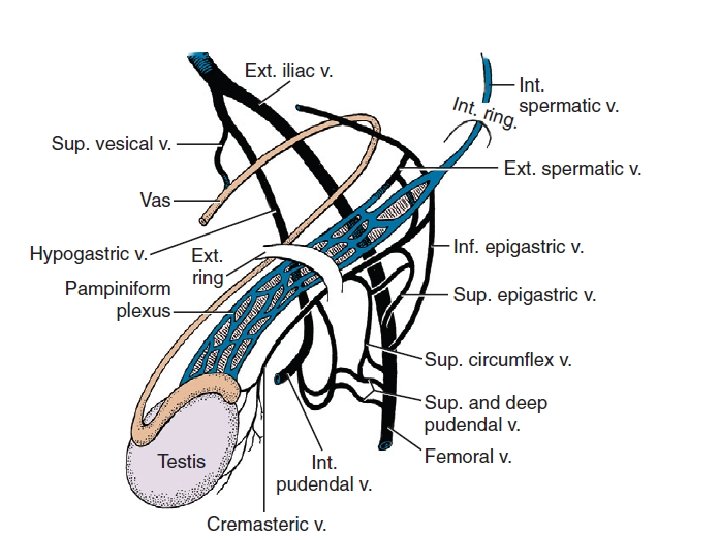

Definition A varicocele is a dilatation of the pampiniform venous plexus and the internal spermatic vein. Varicocele is a well-recognized cause of decreased testicular function. . occurs in approximately 15 -20% of all males and in 40% of infertile males. varicocele are the most common cause of poor sperm production and decreased semen quality. Varicoceles are easy to identify and to surgically correct.

Etiology Varicoceles are much more common (approximately 80 -90%) in the left testicle than in the right because of several anatomic factors, including: 1) the angle at which the left testicular vein enters the left renal vein. 2) the lack of effective antireflux valves at the juncture of the testicular vein and renal vein. 3) the increased renal vein pressure due to its compression between the superior mesenteric artery and the aorta( the nutcracker phenomenon) 4) Increased length of the left testicular vein: The left vein is 8 -10 cm longer than the right testicular vein

80% of men with a left clinical varicocele had bilateral varicoceles revealed by noninvasive radiologic testing. Lt. spermatic vein pressure=10 mm Hg and ends in lt. renal vein which pressure =10 mm. Hg. so any strain can be detected by increase intra abdominal pressure by valsalva m. In Rt. side : Rt. spermatic vein pressure =10 mm Hg and ends in IVC which pressure =ZERO. So due to increase intra abdominal pressure not increasing pressure Over Rt. spermatic vein. Right side varicocele : We shoud consider possible retroperitoneal pathology (eg, renal cell carcinoma) As the cause of spermayic vein compression. Investigate further with approprite ultrasonography Or Ct scanning befor repairing the varicocele.